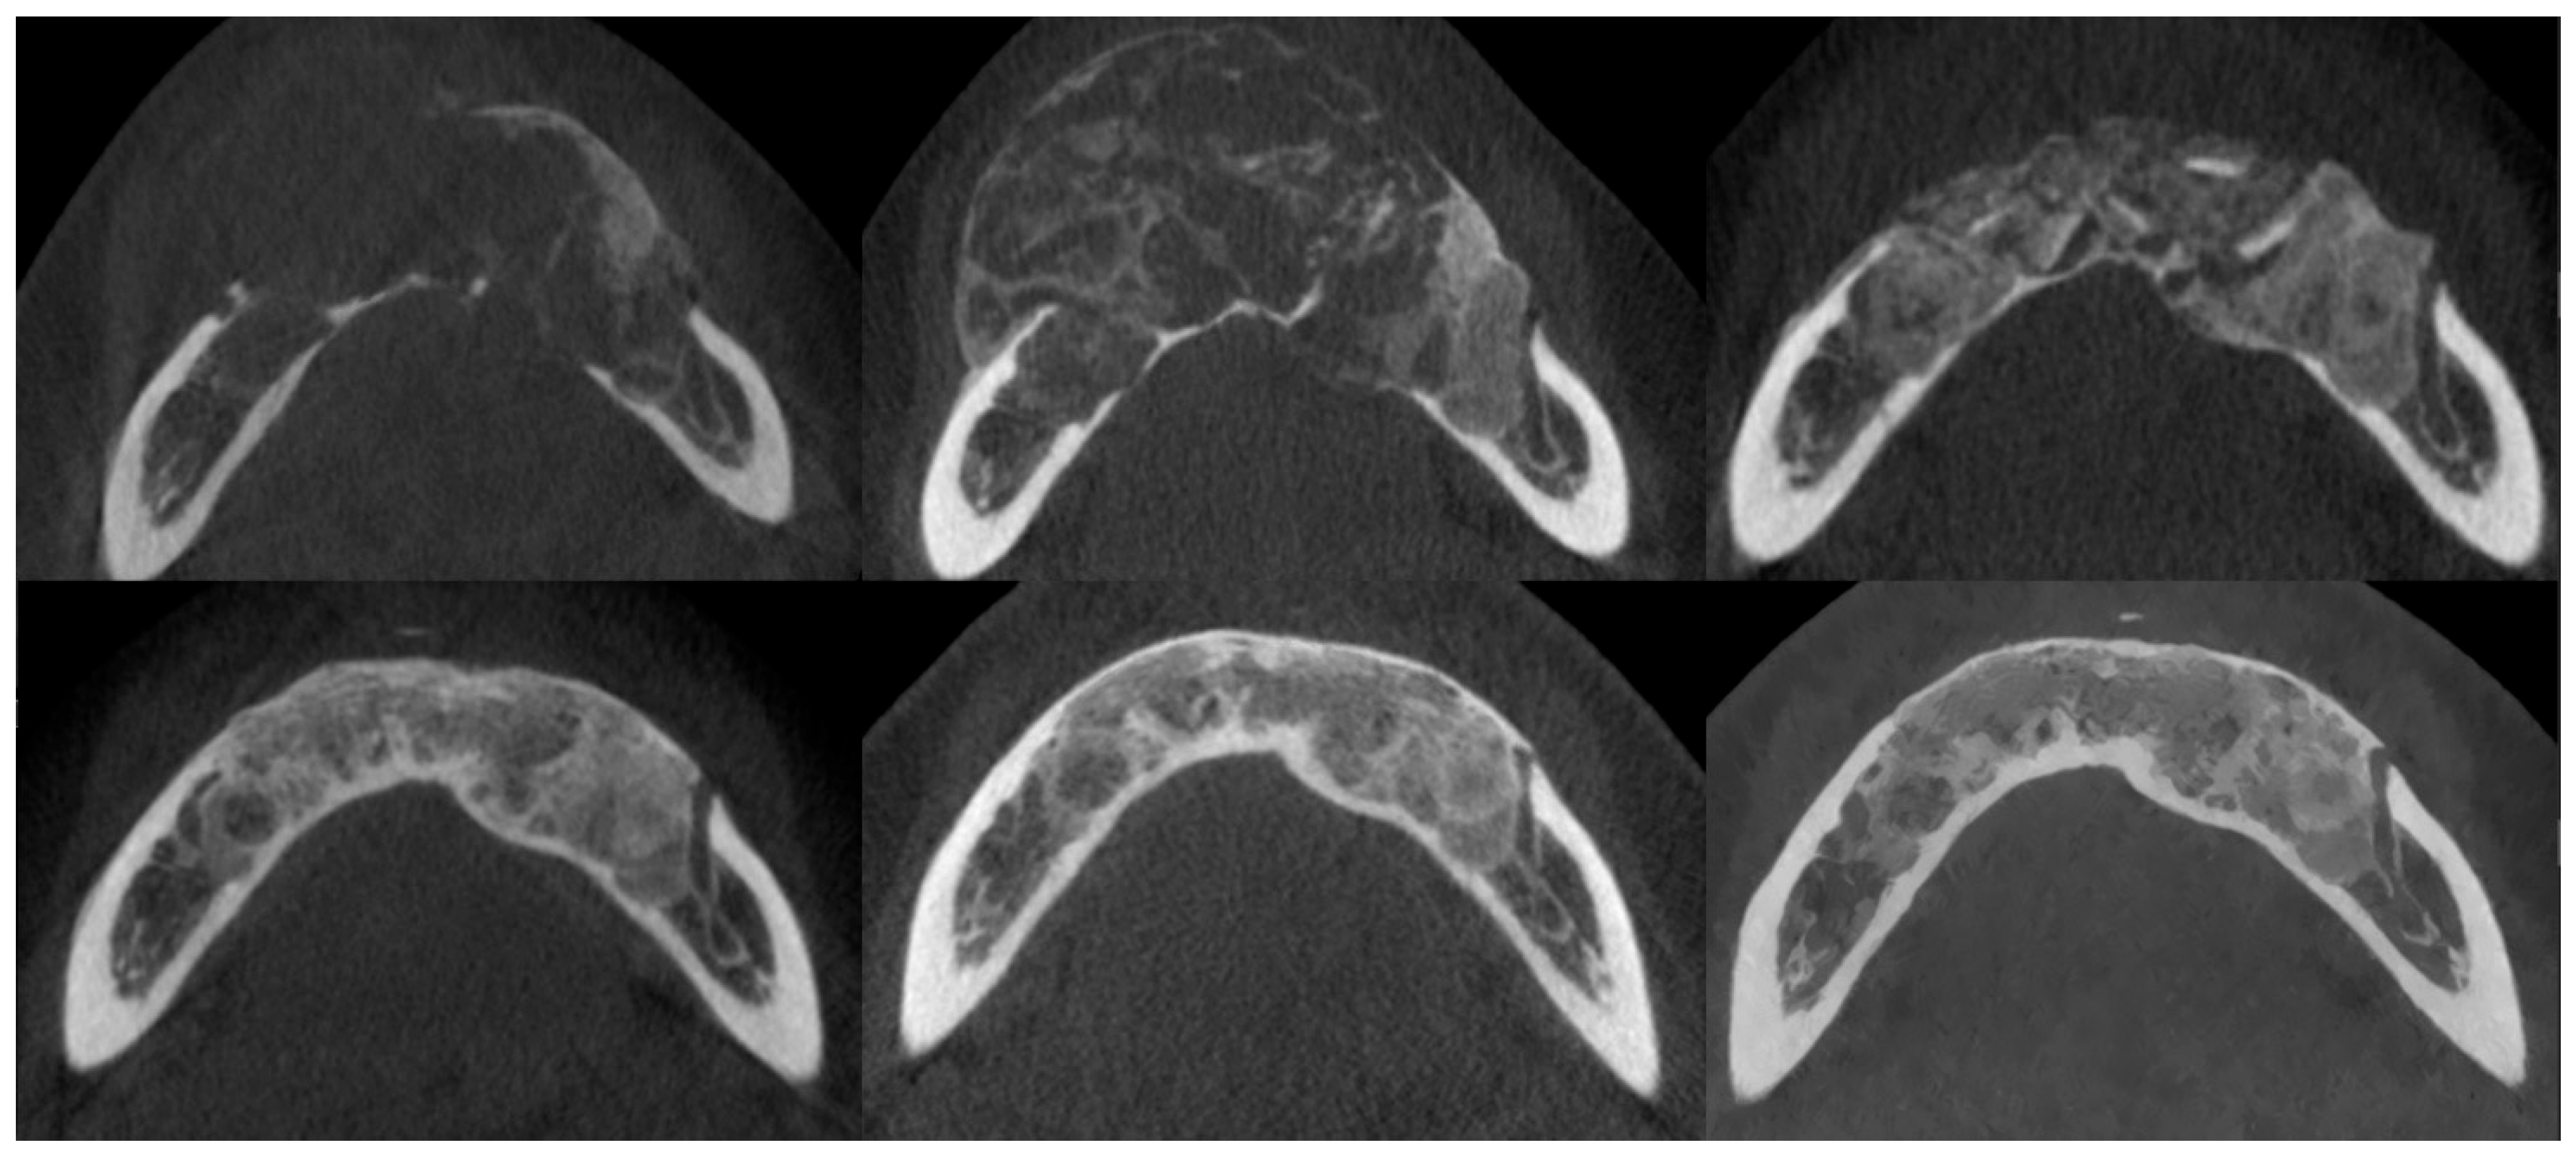

3.3. Osteosclerotic Rim (Peripheral Corticalization)